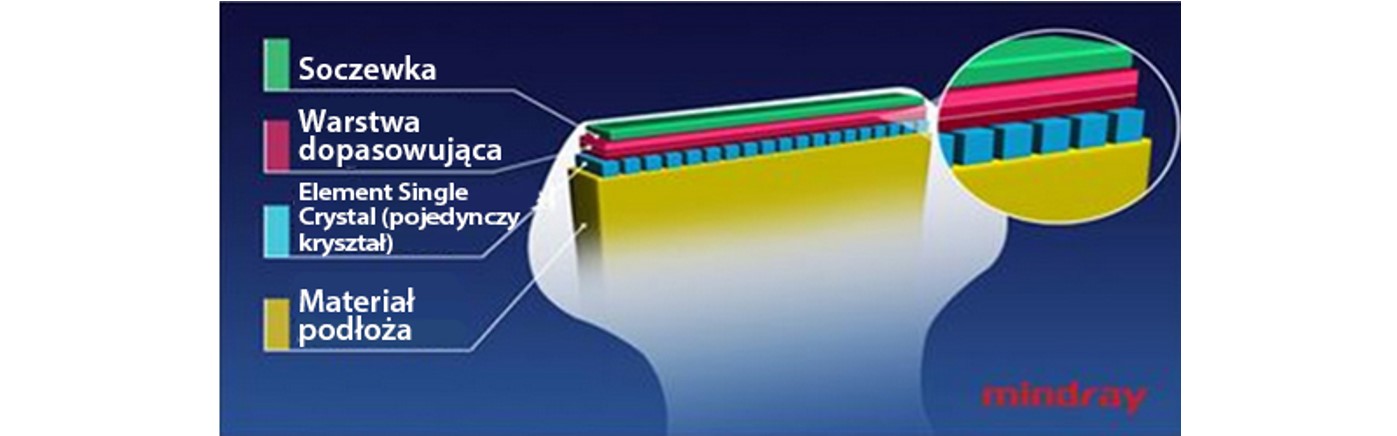

G?owice z zastosowanymi technologiami 3T i Single Crystal (pojedyÅczy kryszta?)

Technologie dostarczaj?ce ostrzejsze obrazy - wszystkie sondy kompatybilne z M9 s? wyposa?one w unikaln? technologi? 3T Firmy Mindray. Dodatkowo technologia Single Crystal (pojedynczego kryszta?u), oferuje lepsz? penetracj? i dynamiczny obraz przep?ywu w trybie Dopplera Kolorowego, zw?aszcza podczas skanowania trudnych przypadkÃģw.